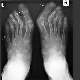

Bunyon